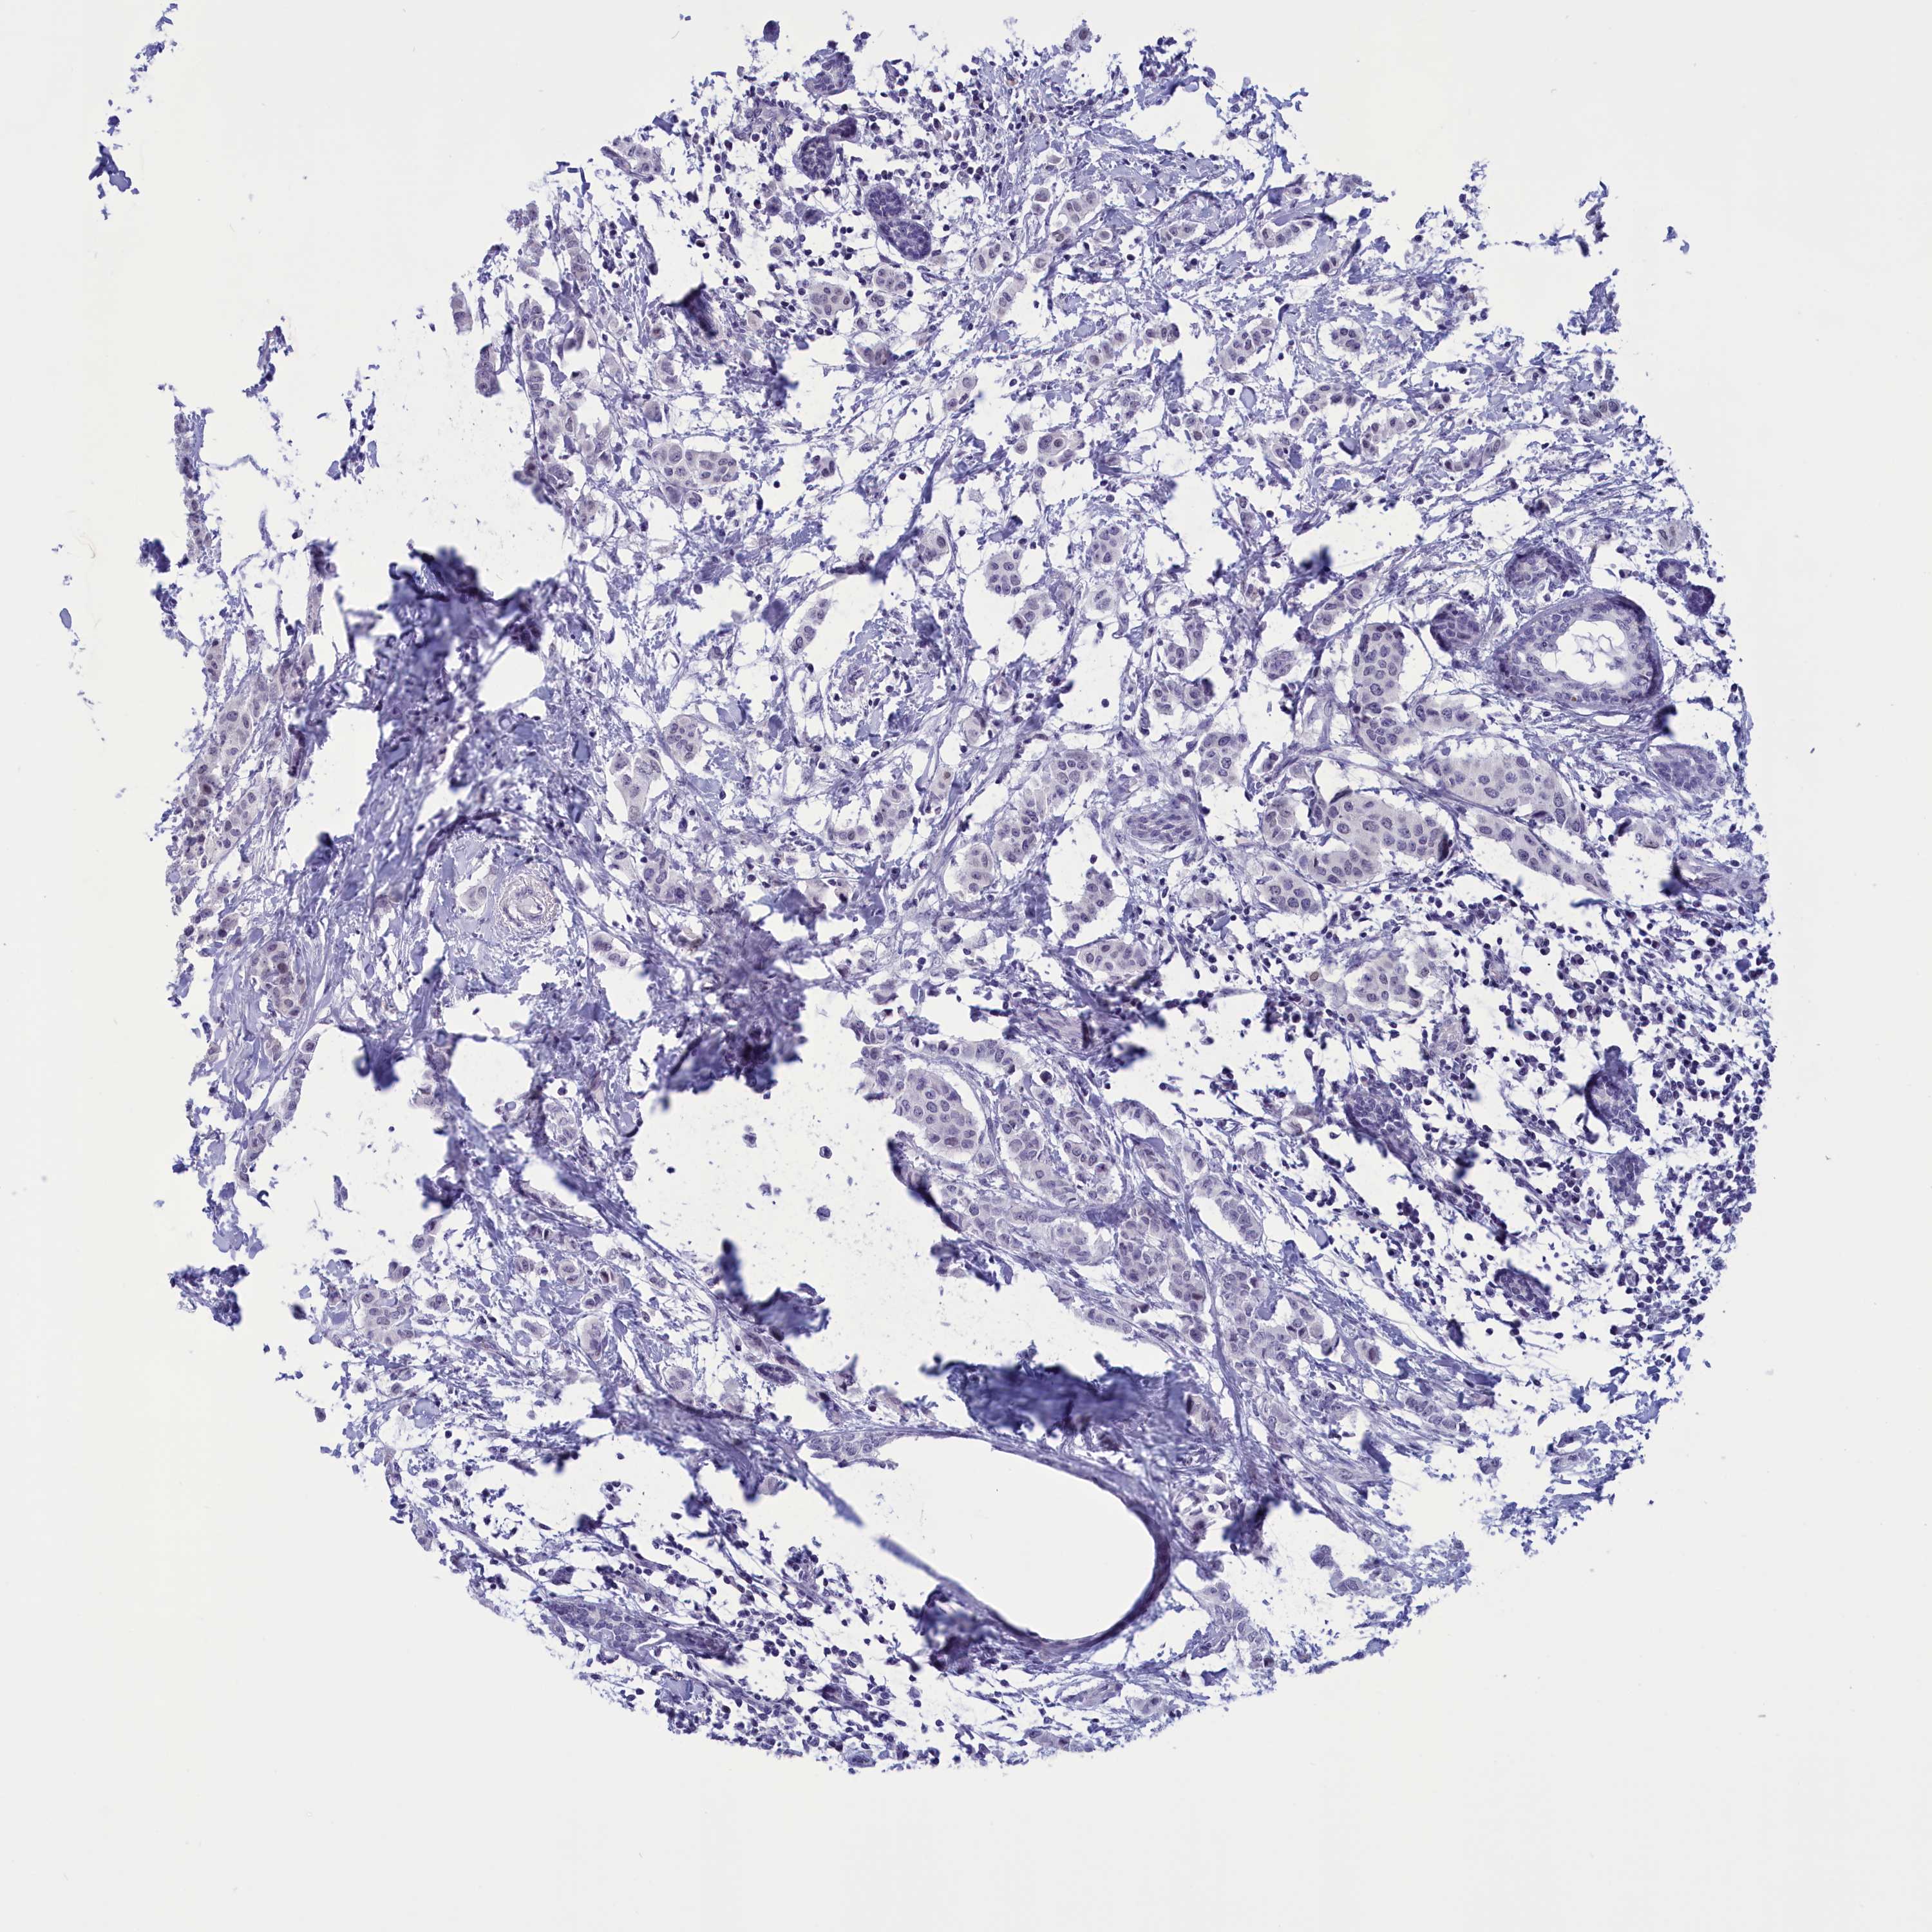

CANCER BREAST CANCER Show tissue menu

BRCA TCGA BRCA VALIDATION PROTEIN EXPRESSION